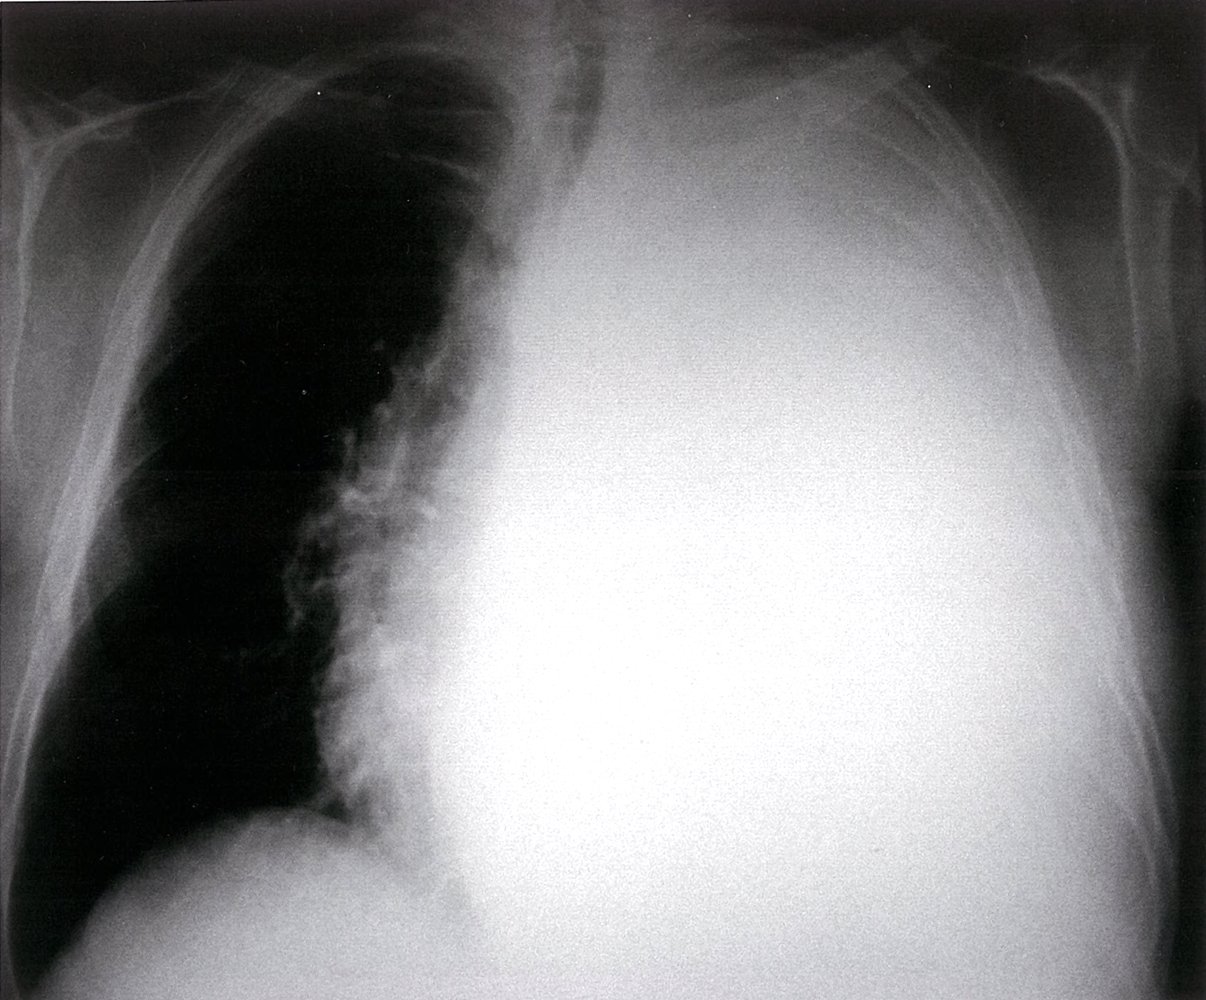

- Reduced air entry

- Unilaterally: Consider pneumothorax, extensive pleural effusion, or hemothorax.

- Hyperressonance: Consider pneumothorax.

- Dullness: Consider consolidation or fluid, e.g., in hemothorax or pleural effusion.